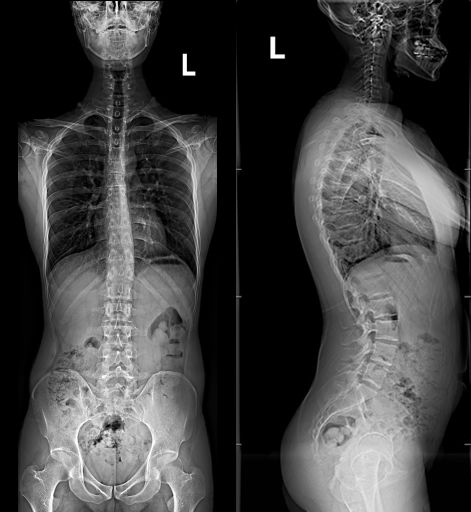

3.脊柱和下肢全长拼接功能——立位拼接和卧位拼接

配合智能可视化功能,只需要患者站上去,鼠标拖动范围即可曝光。这无疑是减轻了技师的操作时间,方便快捷。采用全自动拼接流程,只需要设定拼接起点和终点,其余全自动完成。躺着拍的脊柱全长更是方便了无法站立的患者,为更多患者提供拍片可能性,不受体位干扰。下图为我院骨科门诊要求拍摄的通过拼接实现的脊柱全长正侧位片,椎体影像清晰能完全满足临床需求!